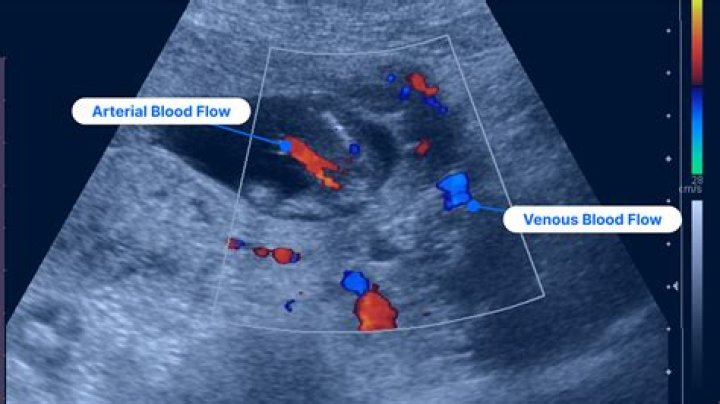

Duplex ultrasonography is an imaging test that uses sound waves to look at the flow of blood in the veins. It can detect blockages or blood clots in the deep veins. It is the standard imaging test to diagnose DVT.

Ultrasound scanning gives a clear picture of soft tissues that do not show up well on x-ray images. Venous ultrasound helps to detect blood clots in the veins of the legs before they become dislodged and pass to the lungs. It can also show the movement of blood within blood vessels.

Duplex ultrasound. This noninvasive test uses sound waves to create pictures of how blood flows through your veins. It’s the standard test for diagnosing DVT . For the test, a technician gently moves a small hand-held device (transducer) on your skin over the body area being studied.